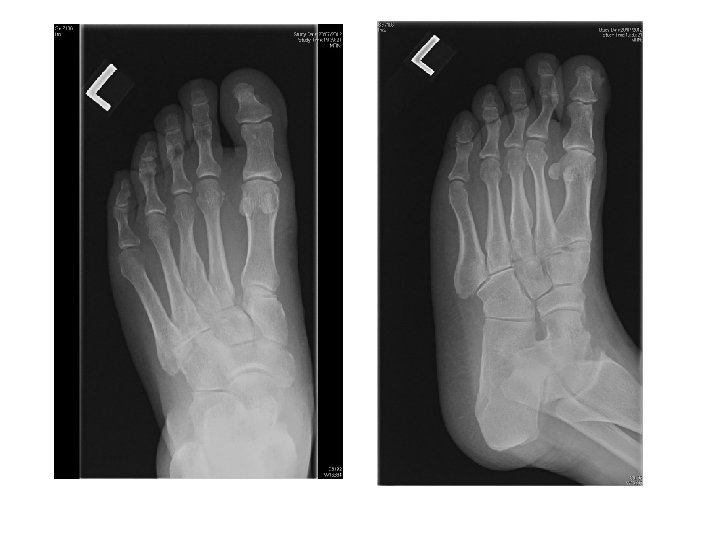

Case 1 • • M/52 Walk unaided to AED c/o left foot sprain few

Case 1 • • M/52 Walk unaided to AED c/o left foot sprain few days ago during working P/E swelling, tender over dorsum of foot

Questions • What were the X ray findings • What was the name of

Questions • What were the X ray findings • What was the name of the sign showed in Xray? • What was this injury call? • What was the classification of this injury • What was the optimal management • What were the important complications